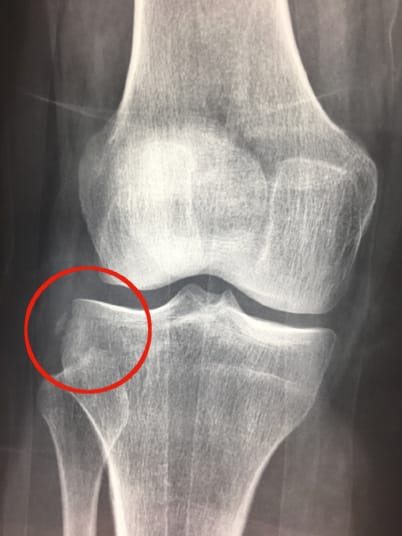

Traumatologie - Orthopédie Mise au point : les plasties extra-articulaires du genou associées aux ligamentoplasties du LCA